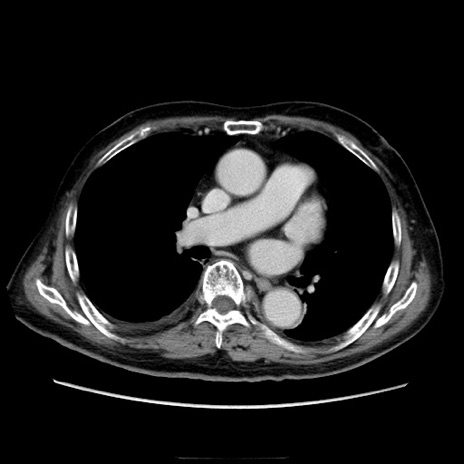

冠状断像

【症例】70歳代男性

【主訴】腹痛

【現病歴】肝硬変・肝細胞癌にてかかりつけの方。約9時間前に食後より腹痛出現。症状が徐々に増悪し、嘔吐出現したため来院。

【既往歴】肝硬変、肝細胞癌(RFA、TACE後)

【身体所見】意識清明、表情苦悶様、BT 36℃、BP 129/78mmHg、P 88bpm、SpO2 97%(RA)、右上腹部から心窩部にかけて圧痛あり、反跳痛なし、筋性防御あり。

【データ】WBC 5800、CRP 0.16